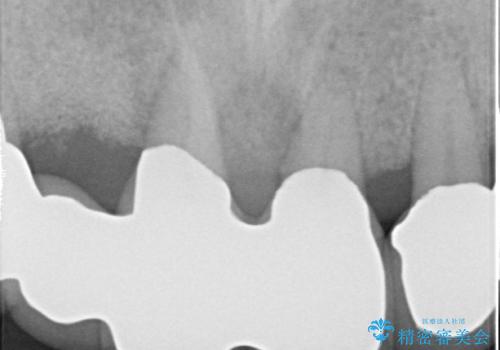

- 歯周病により欠損が生じた歯槽骨、まずは再生治療をおこなう

→治癒後、確定外科を行い完全に歯周ポケットを除去し、最終的に歯周補綴をおこなう

かぶせ物の種類:PFM full bake